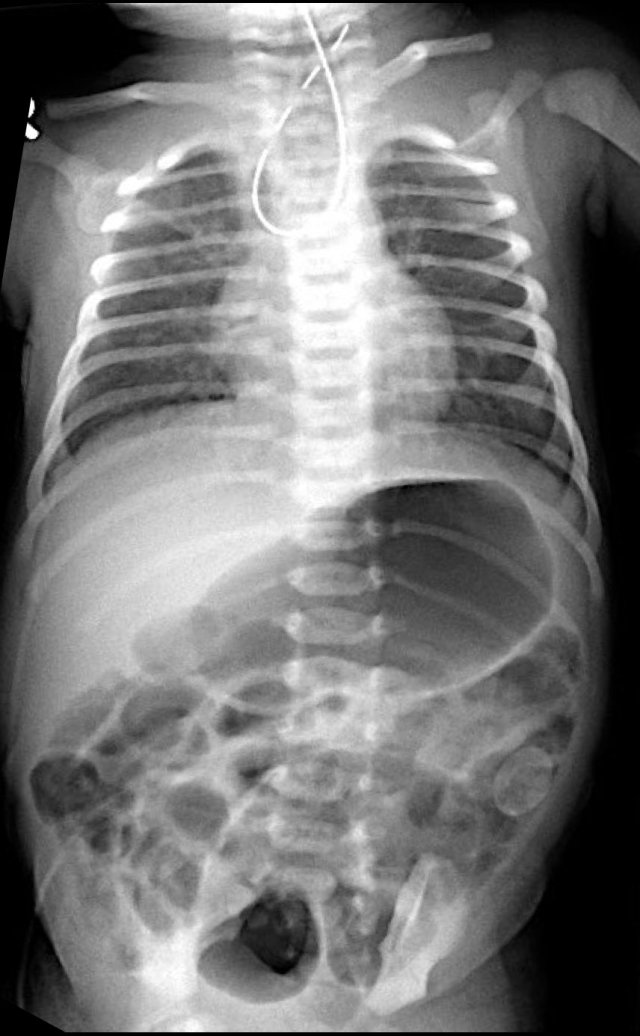

The findings are:

- Multiple dilated small bowel loops

- Pneumatosis intestinalis.

- Pneumoperitoneum.

Diagnosis:

NEC with perforation.